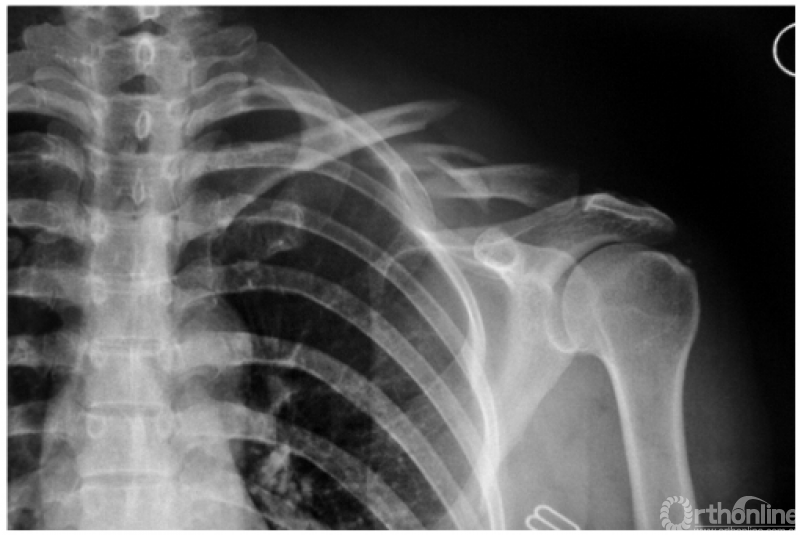

1. 肩锁关节脱位并喙突撕脱骨折

本例虽然肩锁关节发生脱位,但因喙突撕脱骨折而喙锁韧带未断裂,故喙锁间隙正常(图3)。